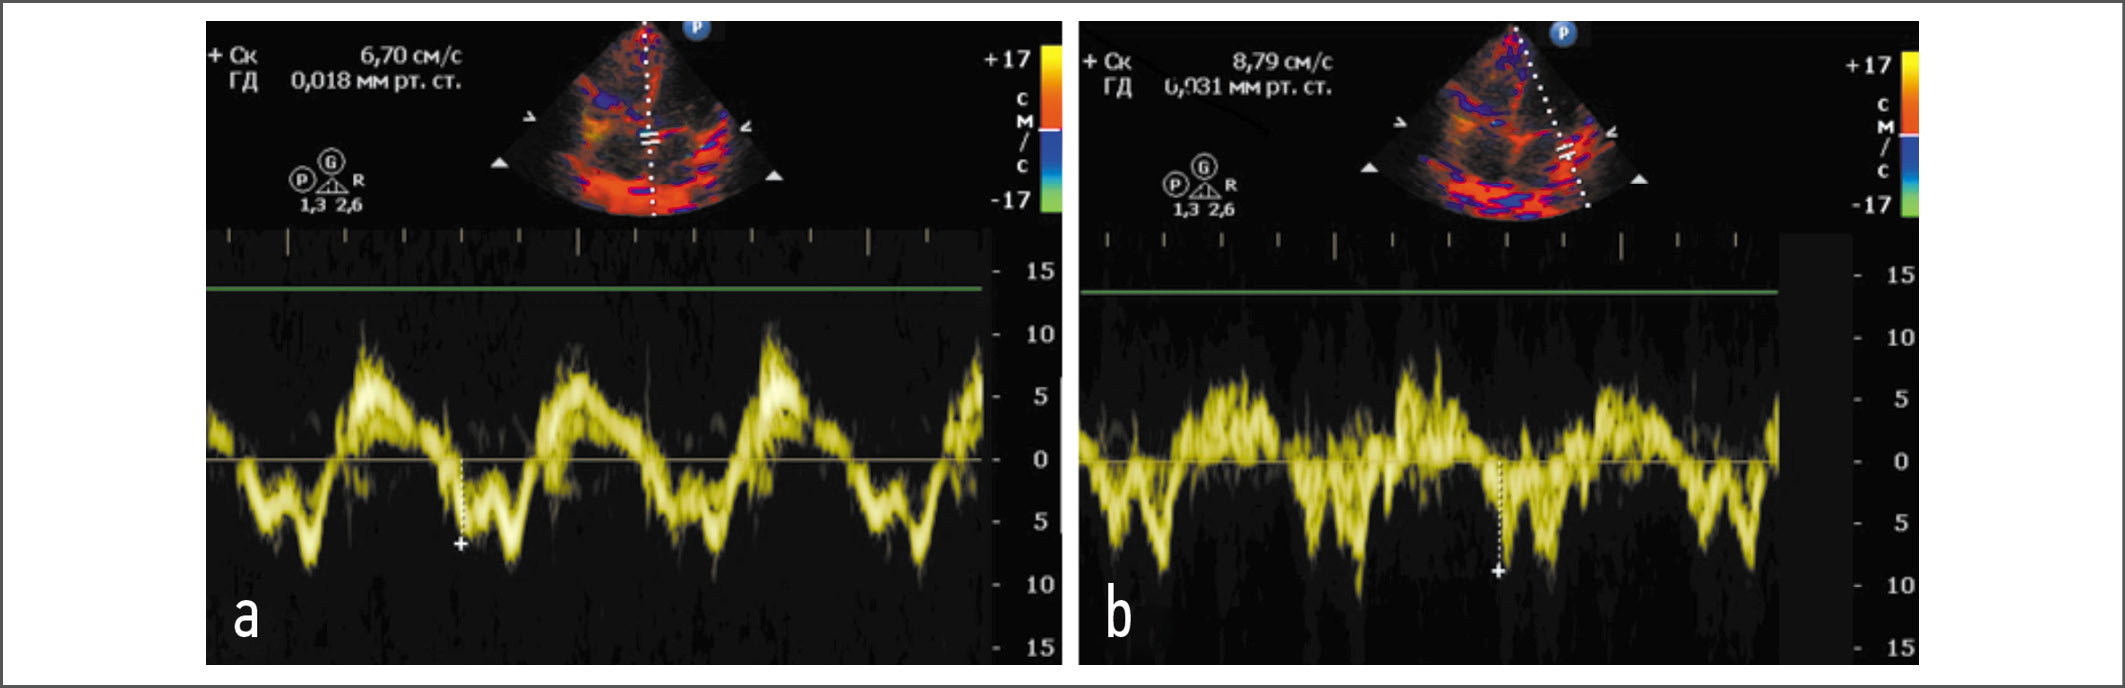

Стандартная электрокардиография: P – 0,11 с, PQ – 0,15 с, QRS – 0,13 с, Q–Tc – 0,47 с. Ритм синусовый, с частотой сердечных сокращений 73 в минуту, полная блокада правой ножки пучка Гиса. По результатам ЭхоКГ установлено, что миокард не утолщен, индекс массы миокарда ЛЖ (ИММЛЖ) составляет 76 г/м², полости сердца не расширены. Индекс объема левого предсердия (ЛП) – 22 мл/м². Фракция выброса ЛЖ по Симпсону – 71%. Ударный объем ЛЖ незначительно снижен (42 мл). Нарушений кинетики миокарда не выявлено. При допплеровской оценке трансмитрального кровотока получено расчетное отношение максимальной скорости раннего наполнения к максимальной скорости позднего наполнения в диастолу (Е/А, ед), составившее 1,4. Пиковая тканевая скорость раннего диастолического смещения (e’) септальной и латеральной частей кольца митрального клапана оказалась равной 6,7 и 8,79 см/с соответственно, усредненные значения показателей e’ и Е/e’ – 7,5 и 17,3 ед соответственно. Отмечена трикуспидальная регургитация 2-й степени, скорость которой составила 3,23 м/с. Створки митрального и аортального клапанов уплотнены. Расчетное давление в легочной артерии – 45 мм рт. ст. Листки перикарда не утолщены, выпота в полости перикарда нет. На рис. 1, 2 представлены результаты допплерографии.

Рис. 1. Тканевая допплерография области кольца митрального клапана. На фрагментах a и b отмечено снижение септальной и латеральной миокардиальной скоростей кольца митрального клапана до 6,7 и 8,79 см/с соответственно.

Fig. 1. Tissue dopplerography of the mitral valve annulus. Fragments a and b showed a decrease in septal and lateral myocardial velocities of the mitral valve ring to 6,7 and 8,79 cm/s, respectively.

В ходе ЭхоКГ у нашей пациентки установлены признаки ДДЛЖ псевдонормального типа. О факте диастолической дисфункции свидетельствовали 3 из 4 критериев, принятых для пациентов с синусовым ритмом и нормальной фракцией выброса ЛЖ: Е/e’>14; e’ септальная <7 см/с и e’ латеральная <10 см/с; скорость трикуспидальной регургитации >2,8 м/с [14]. Отсутствовал единственный (4-й) критерий – дилатация ЛП. С учетом нахождения параметра трансмитрального кровотока Е/А в диапазоне >0,8 и <2,0 нами констатирован псевдонормальный тип (2-я степень) ДДЛЖ. Нормальный объем ЛП возможно рассматривать как один из признаков того, что ДДЛЖ находится в относительно компенсированной стадии.